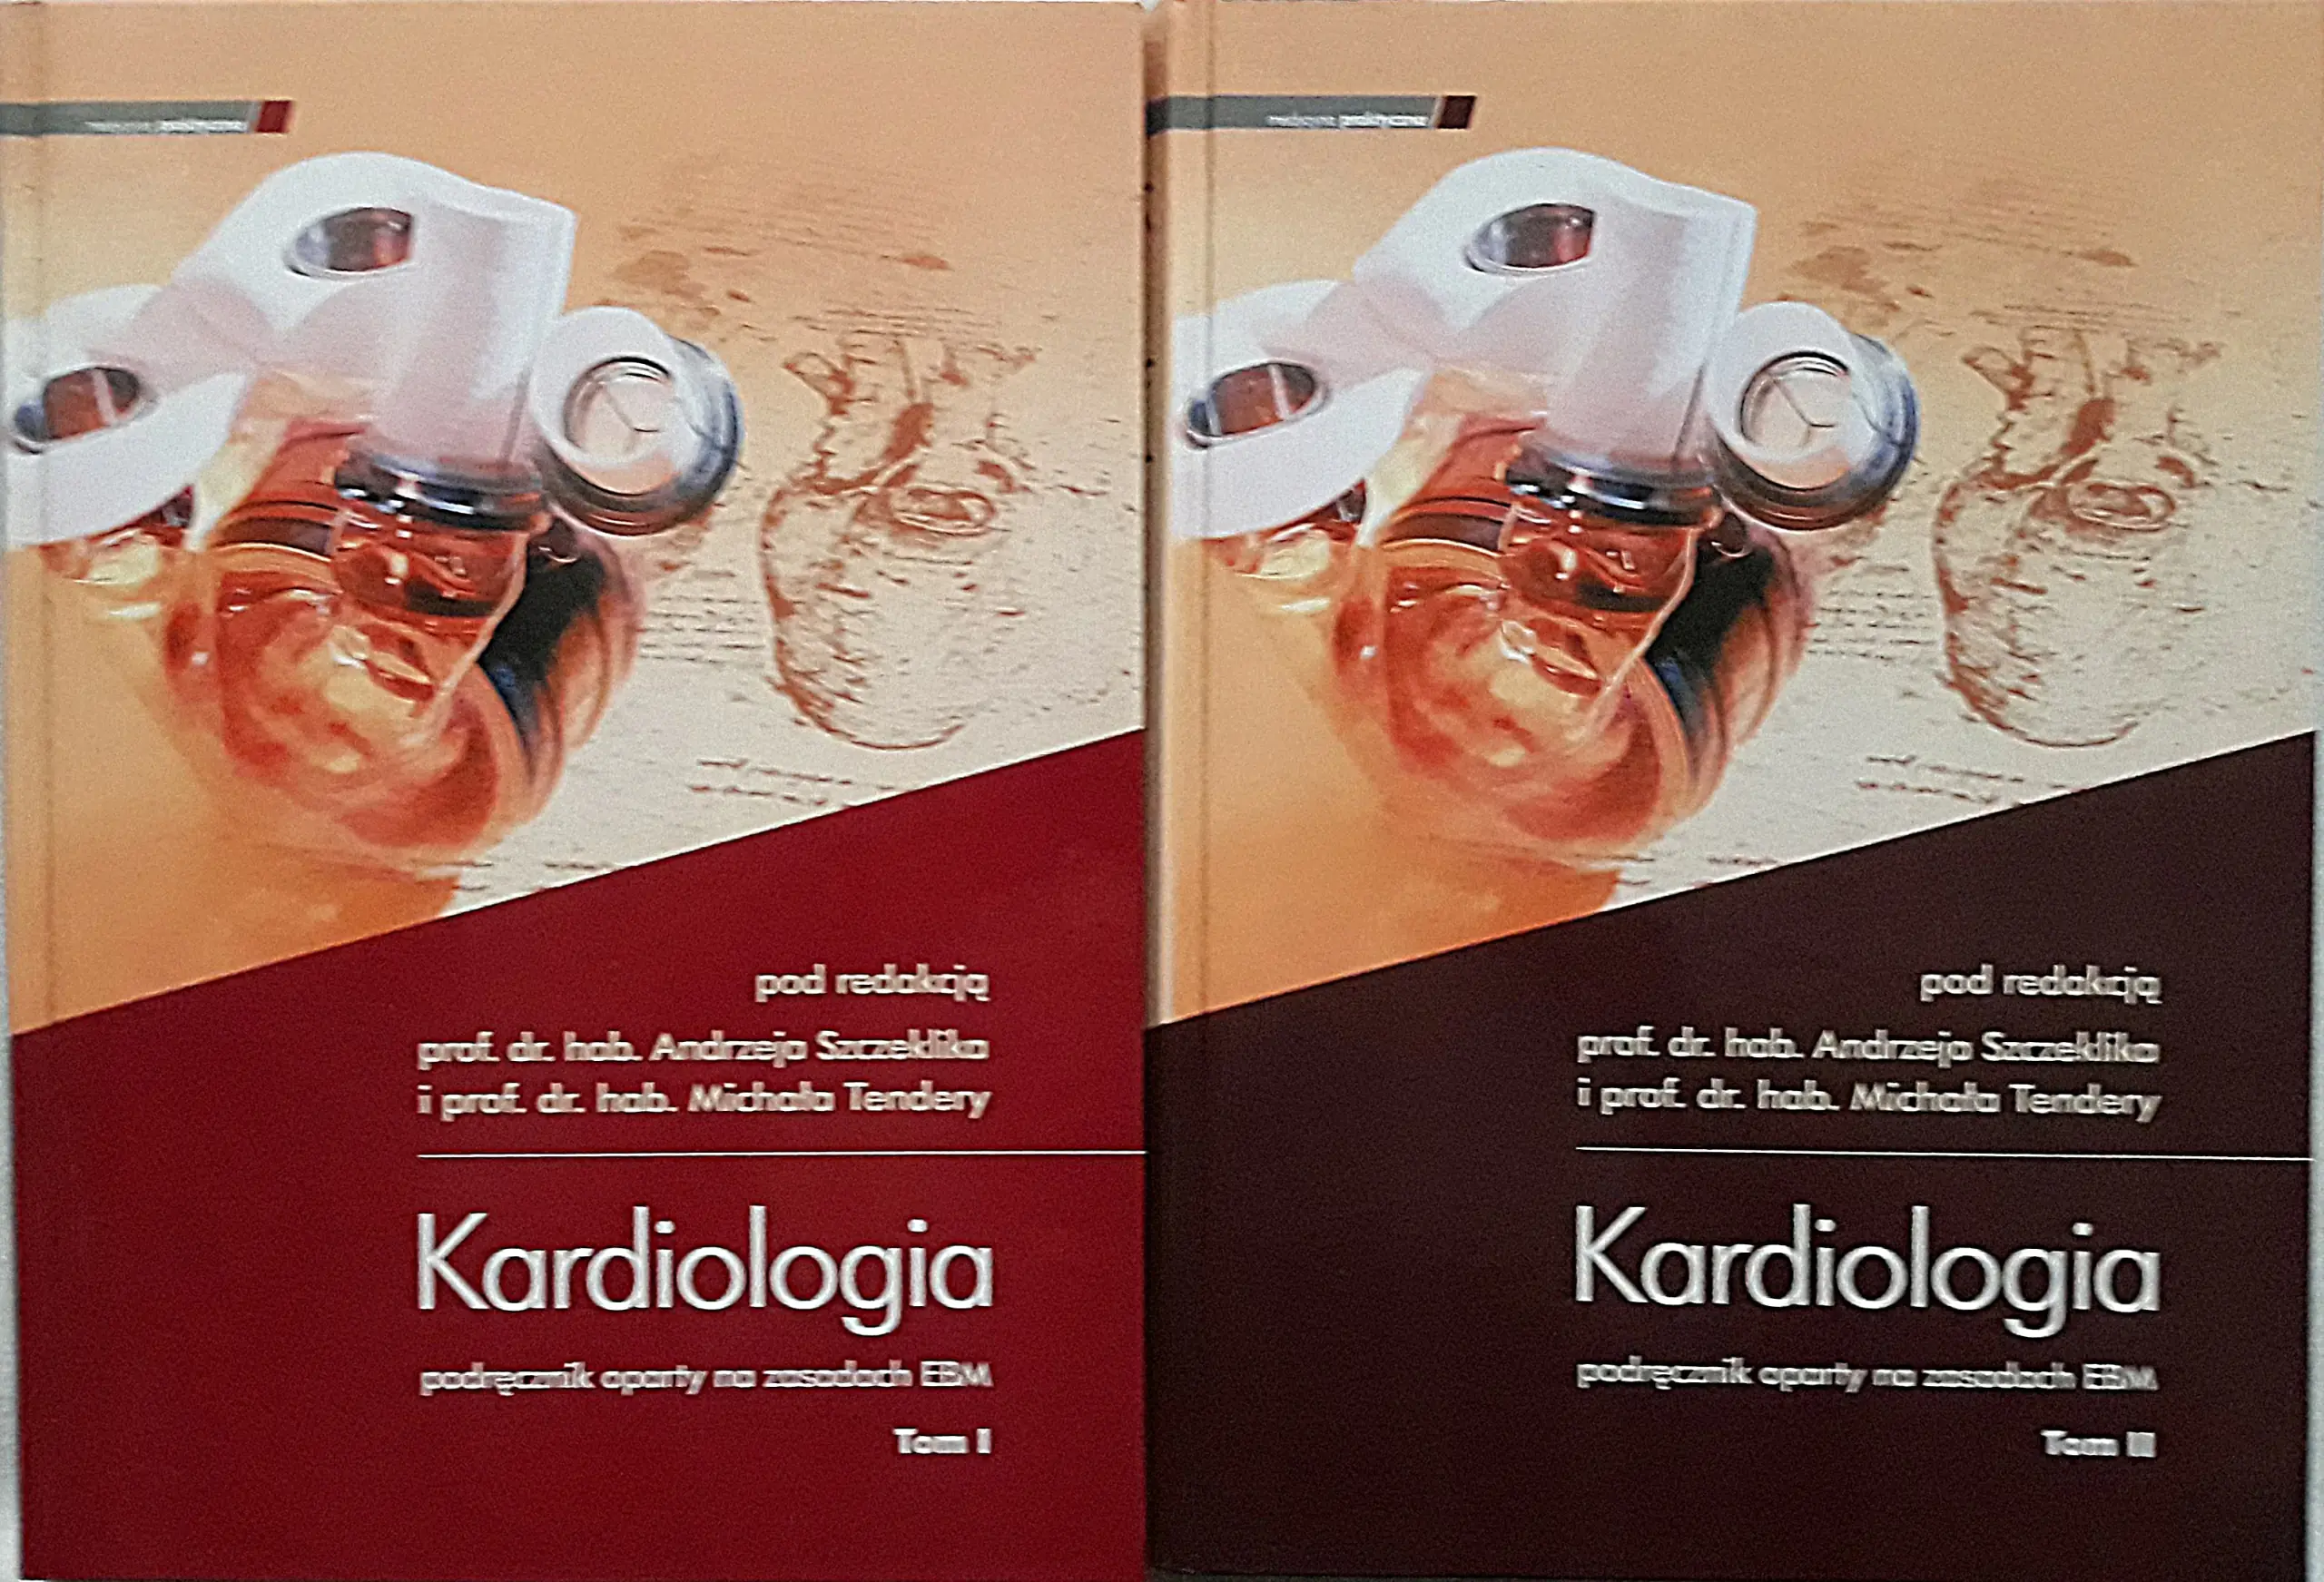

Opis książki przedstawia najnowsze wytyczne związane z różnymi aspektami kardiologii. Pierwsza część koncentruje się na opiece nad kobietami w ciąży, które zmagają się z chorobami serca. Nowe klasyfikacje dotyczą oceny ryzyka sercowego, a także uwzględniają wady zastawkowe zarówno nabyte, jak i wrodzone, nadciśnienie tętnicze i płucne, kardiomiopatie oraz chorobę wieńcową.

Dalsza część książki opisuje procesy rewaskularyzacyjne w kontekście stabilnej choroby wieńcowej oraz w przypadkach STEMI i nSTEMI. Książka przedstawia również zaktualizowaną definicję zawału serca. Aby ułatwić przyswojenie zaleceń, zastosowano wizualizacje diagnostyczne i postępowanie przy użyciu echokardiografii.

Osobny rozdział poświęcono elektrokardioterapii, szczegółowo omawiając działania niepożądane oraz procedury usuwania elektrod. Ponadto, książka porusza zasady kompleksowego obrazowania dorosłych pacjentów z wrodzonymi wadami serca, co stanowi istotny element całościowego podejścia do diagnostyki.

Opis książki przedstawia najnowsze wytyczne związane z różnymi aspektami kardiologii. Pierwsza część koncentruje się na opiece nad kobietami w ciąży, które zmagają się z chorobami serca. Nowe klasyfikacje dotyczą oceny ryzyka sercowego, a także uwzględniają wady zastawkowe zarówno nabyte, jak i wrodzone, nadciśnienie tętnicze i płucne, kardiomiopatie oraz chorobę wieńcową.

Dalsza część książki opisuje procesy rewaskularyzacyjne w kontekście stabilnej choroby wieńcowej oraz w przypadkach STEMI i nSTEMI. Książka przedstawia również zaktualizowaną definicję zawału serca. Aby ułatwić przyswojenie zaleceń, zastosowano wizualizacje diagnostyczne i postępowanie przy użyciu echokardiografii.

Osobny rozdział poświęcono elektrokardioterapii, szczegółowo omawiając działania niepożądane oraz procedury usuwania elektrod. Ponadto, książka porusza zasady kompleksowego obrazowania dorosłych pacjentów z wrodzonymi wadami serca, co stanowi istotny element całościowego podejścia do diagnostyki.